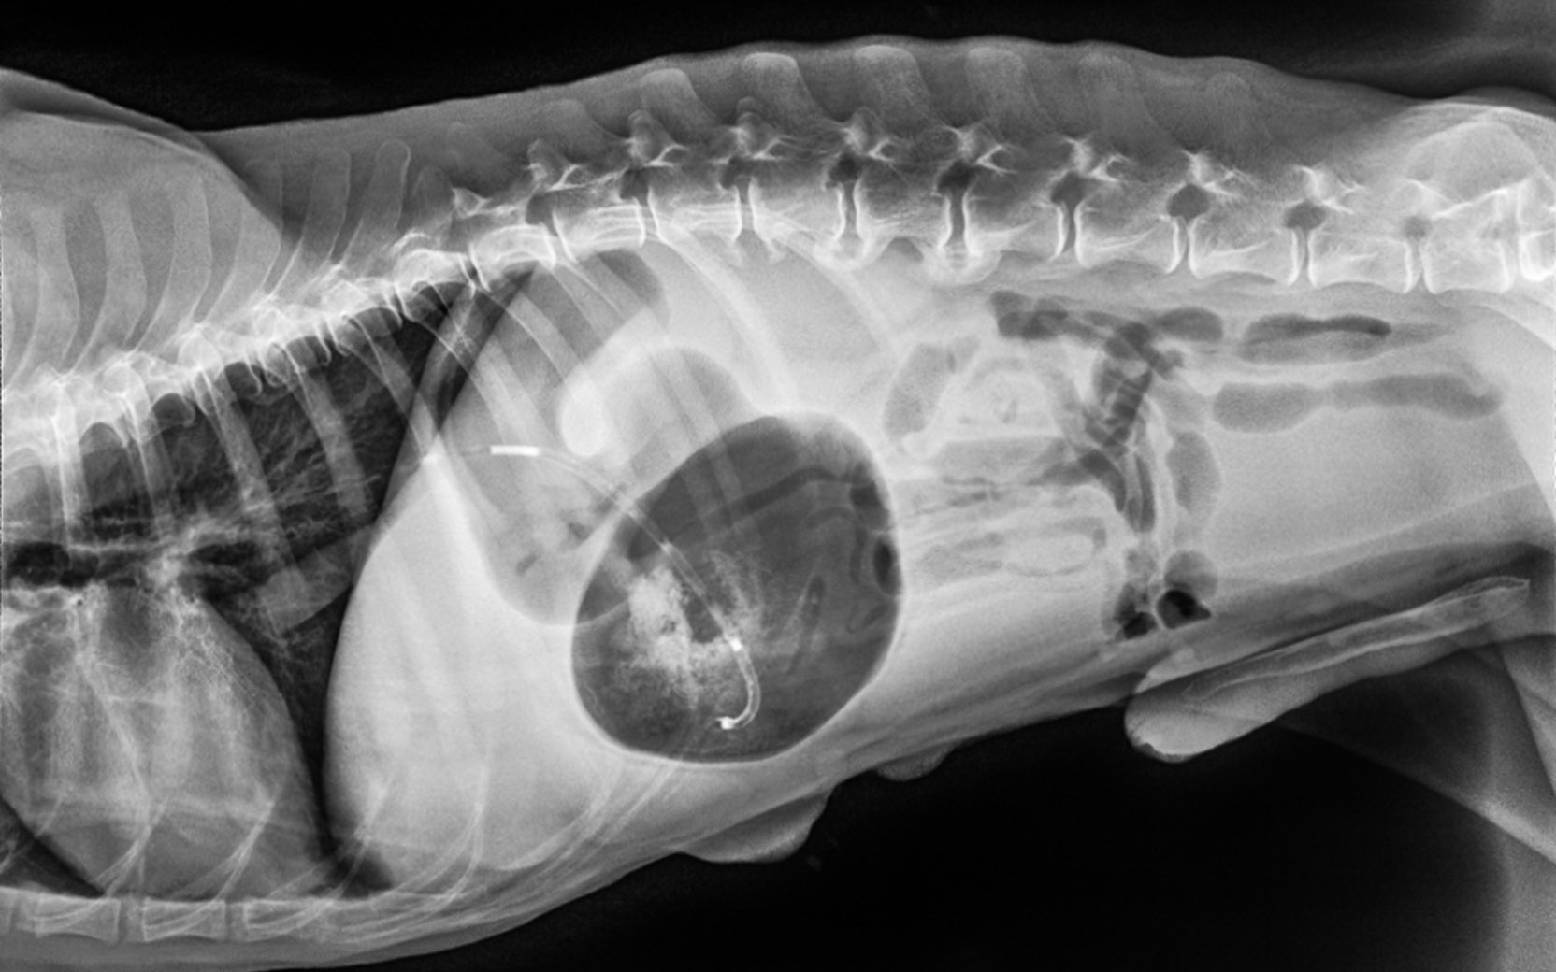

Die Symptome dieser Erkrankung sind derart charakteristisch, dass eine Verdachtsdiagnose durch den/die Tierärzt:in meist schon am Telefon gestellt werden kann. Dieser Verdacht kann dann in der Klinik durch die allgemeine und die röntgenologische Untersuchung der Bauchhöhle schnell bestätigt werden.

Die ersten Anzeichen dieser akut auftretenden Erkrankung sind meist unspezifisch. Zu Beginn kommt es erst nur zu vermehrter Gasbildung, wodurch sich der Magen ausdehnt. Der Hund beginnt plötzlich und meist aus einer Ruhephase heraus unruhig zu werden und hin und her zu laufen. Da der Magen zwischen Speiseröhre und Dünndarm nur locker aufgehängt ist, kann er sich nun im aufgegasten Zustand um die eigene Achse drehen. Milz und Bauchspeicheldrüse werden mitgezogen und Mageneingang und –ausgang, einschließlich der dort liegenden Blutgefäße, werden abgeschnürt. Verdauungsgase können nicht mehr entweichen und die Blutzufuhr wird unterbrochen, so dass es zu Kreislaufstörungen kommt. Der Magen bläht sich immer weiter auf, das Gewebe droht abzusterben und die umliegenden Organe werden durch den Druck des Magens ebenfalls stark belastet. Die Atmung des Hundes wird deutlich schwerer, er krümmt den Rücken, speichelt und versucht zu erbrechen. Aufgrund des zugedrehten Mageneingangs bleiben diese Versuche jedoch ohne Erfolg. Auffällig ist der zunehmend aufgeblähte und gespannte Bauch. Wird der Hund in diesem Stadium nicht unverzüglich in eine Tierklinik gebracht und behandelt, droht ein tödliches Kreislaufversagen.